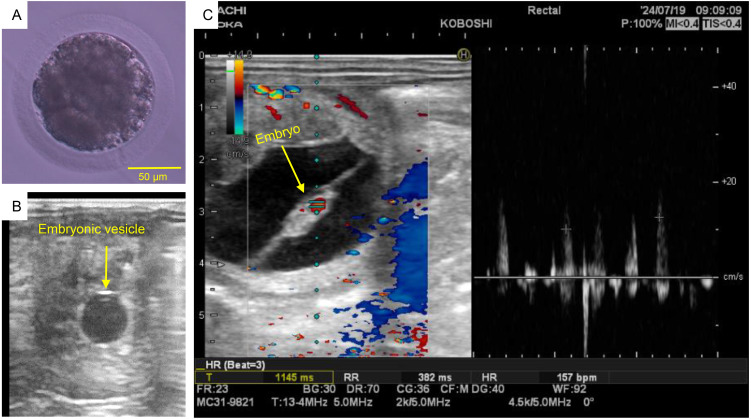

This study evaluated the viability of in vitro embryo production using ovum pick-up (OPU) and intracytoplasmic sperm injection (ICSI) as breeding techniques for pure and crossbred Hokkaido native ponies (n = 9). Oocytes were collected using transvaginal ultrasound-guided follicle aspiration. ICSI was performed on in vitro matured oocytes using frozen semen. Embryonic cultures were monitored using time-lapse cinematography. Blastocysts were cryopreserved and, after thawing, were transferred non-surgically into recipient mares. Over nine OPU sessions, the mean number of aspirated follicles was 23.9 (range, 13-49). The oocyte recovery and maturation rates were 35.3% (76/215) and 61.5% (40/65), respectively. The cleavage rate was 57.5% (23/40). Of cleaved embryos, 56.5% (13/23) were arrested at the 4-cell to 8-cell stage, and five developed into early-blastocyst. Three embryos were transferred, resulting in a successful pregnancy. In conclusion, OPU-ICSI is a viable assisted reproductive technology for enhancing the population of Japanese native horses.